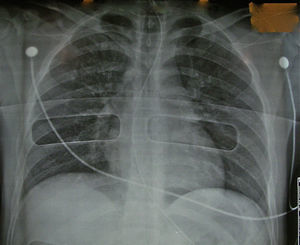

Radiografía de tórax normal.

Radiografía del tórax normal.

Con estos resultados decidimos iniciar la fase clínica y realizamos el primer trasplante pulmonar con un donante en asistolia extrahospitalario mediante «preservación en bitermia» en junio de 2010 a una paciente de 49 años con déficit de alfa-1 antitripsina. Realizamos un trasplante bipulmonar con éxito, con una magnífica función pulmonar tras más de 12h de isquemia total. Desde entonces, entre junio de 2010 y julio de 2011 hemos valorado 15 donantes en asistolia. La radiografía del tórax fue normal en 6 donantes (40%) (fig. 2), presentaban infiltrados pulmonares 7 donantes, en uno la radiografía era de mala calidad y en otro no se pudo realizar. La broncoscopia fue normal en 8 donantes (53%), 3 presentaban abundantes secreciones hemáticas en la vía aérea y en 2 había datos de broncoaspiración.

En cuanto a los donantes en asistolia extrahospitalarios que hemos valorado, observamos que la información de la radiografía del tórax es importante, identificando patología pulmonar en la mitad de los casos. Probablemente los procesos que acompañan al paro cardiaco, como son las arritmias y el fracaso cardiaco, pueden condicionar la aparición de edema pulmonar cardiogénico. De igual forma, la broncoscopia aporta mucha información en cuanto a la presencia de broncoaspiración y secreciones hemáticas que invalidan el injerto como apto para el trasplante.